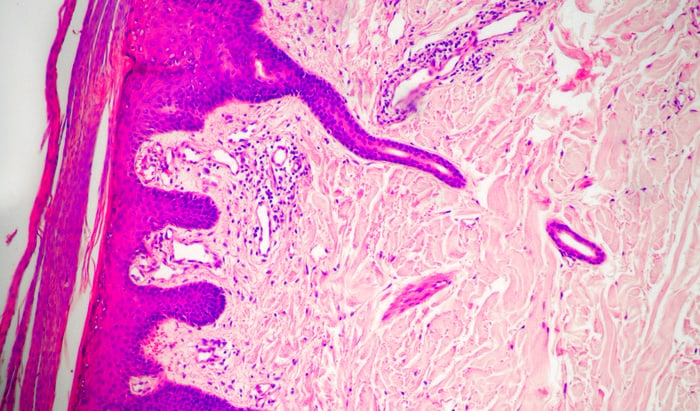

New treatment option for psoriasis discovered: Psoriasis is one of the most common chronic inflammatory skin diseases, affecting around 250,000 people in Austria. While previous treatment approaches have mainly focused on inhibiting pro-inflammatory immune cells, a study led by MedUni Vienna shows that it is possible to restore the function of certain anti-inflammatory immune cells […]